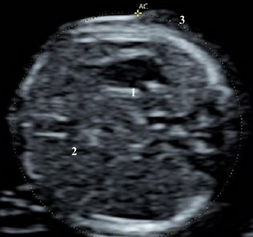

What is the feral lie based on the anatomy showed?

Vertex spine up

Label the anatomy with the arrows

A. Umb. vein

B. Liver

C. Stomach

D. Spine